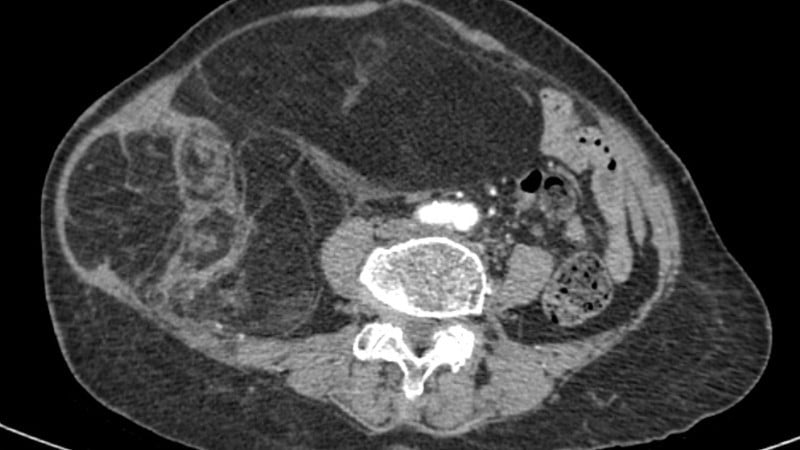

Anteriormente, o paciente (76 anos) foi hospitalizado devido a um rápido aumento de volume abdominal, tensão e deformação da região hipocôndrio-costal direita nos últimos 3 meses. O exame clínico e os exames de imagem mostraram uma massa retroperitoneal, medindo 28x15cm, com estrutura mista de tecido adiposo e sólido, comprimindo os órgãos abdominais, mas sem sinais de invasão de órgãos adjacentes. Combinando os achados clínicos e de imagem, o paciente foi diagnosticado com lipossarcoma retroperitoneal.

Após consulta multidisciplinar, a paciente foi encaminhada para cirurgia radical de remoção do tumor. O cirurgião realizou a dissecção cuidadosamente ao longo do plano anatômico, controlando os pequenos vasos sanguíneos para evitar danos aos órgãos adjacentes. O tumor foi removido integralmente, pesando cerca de 4 kg e medindo 28 x 15 cm.